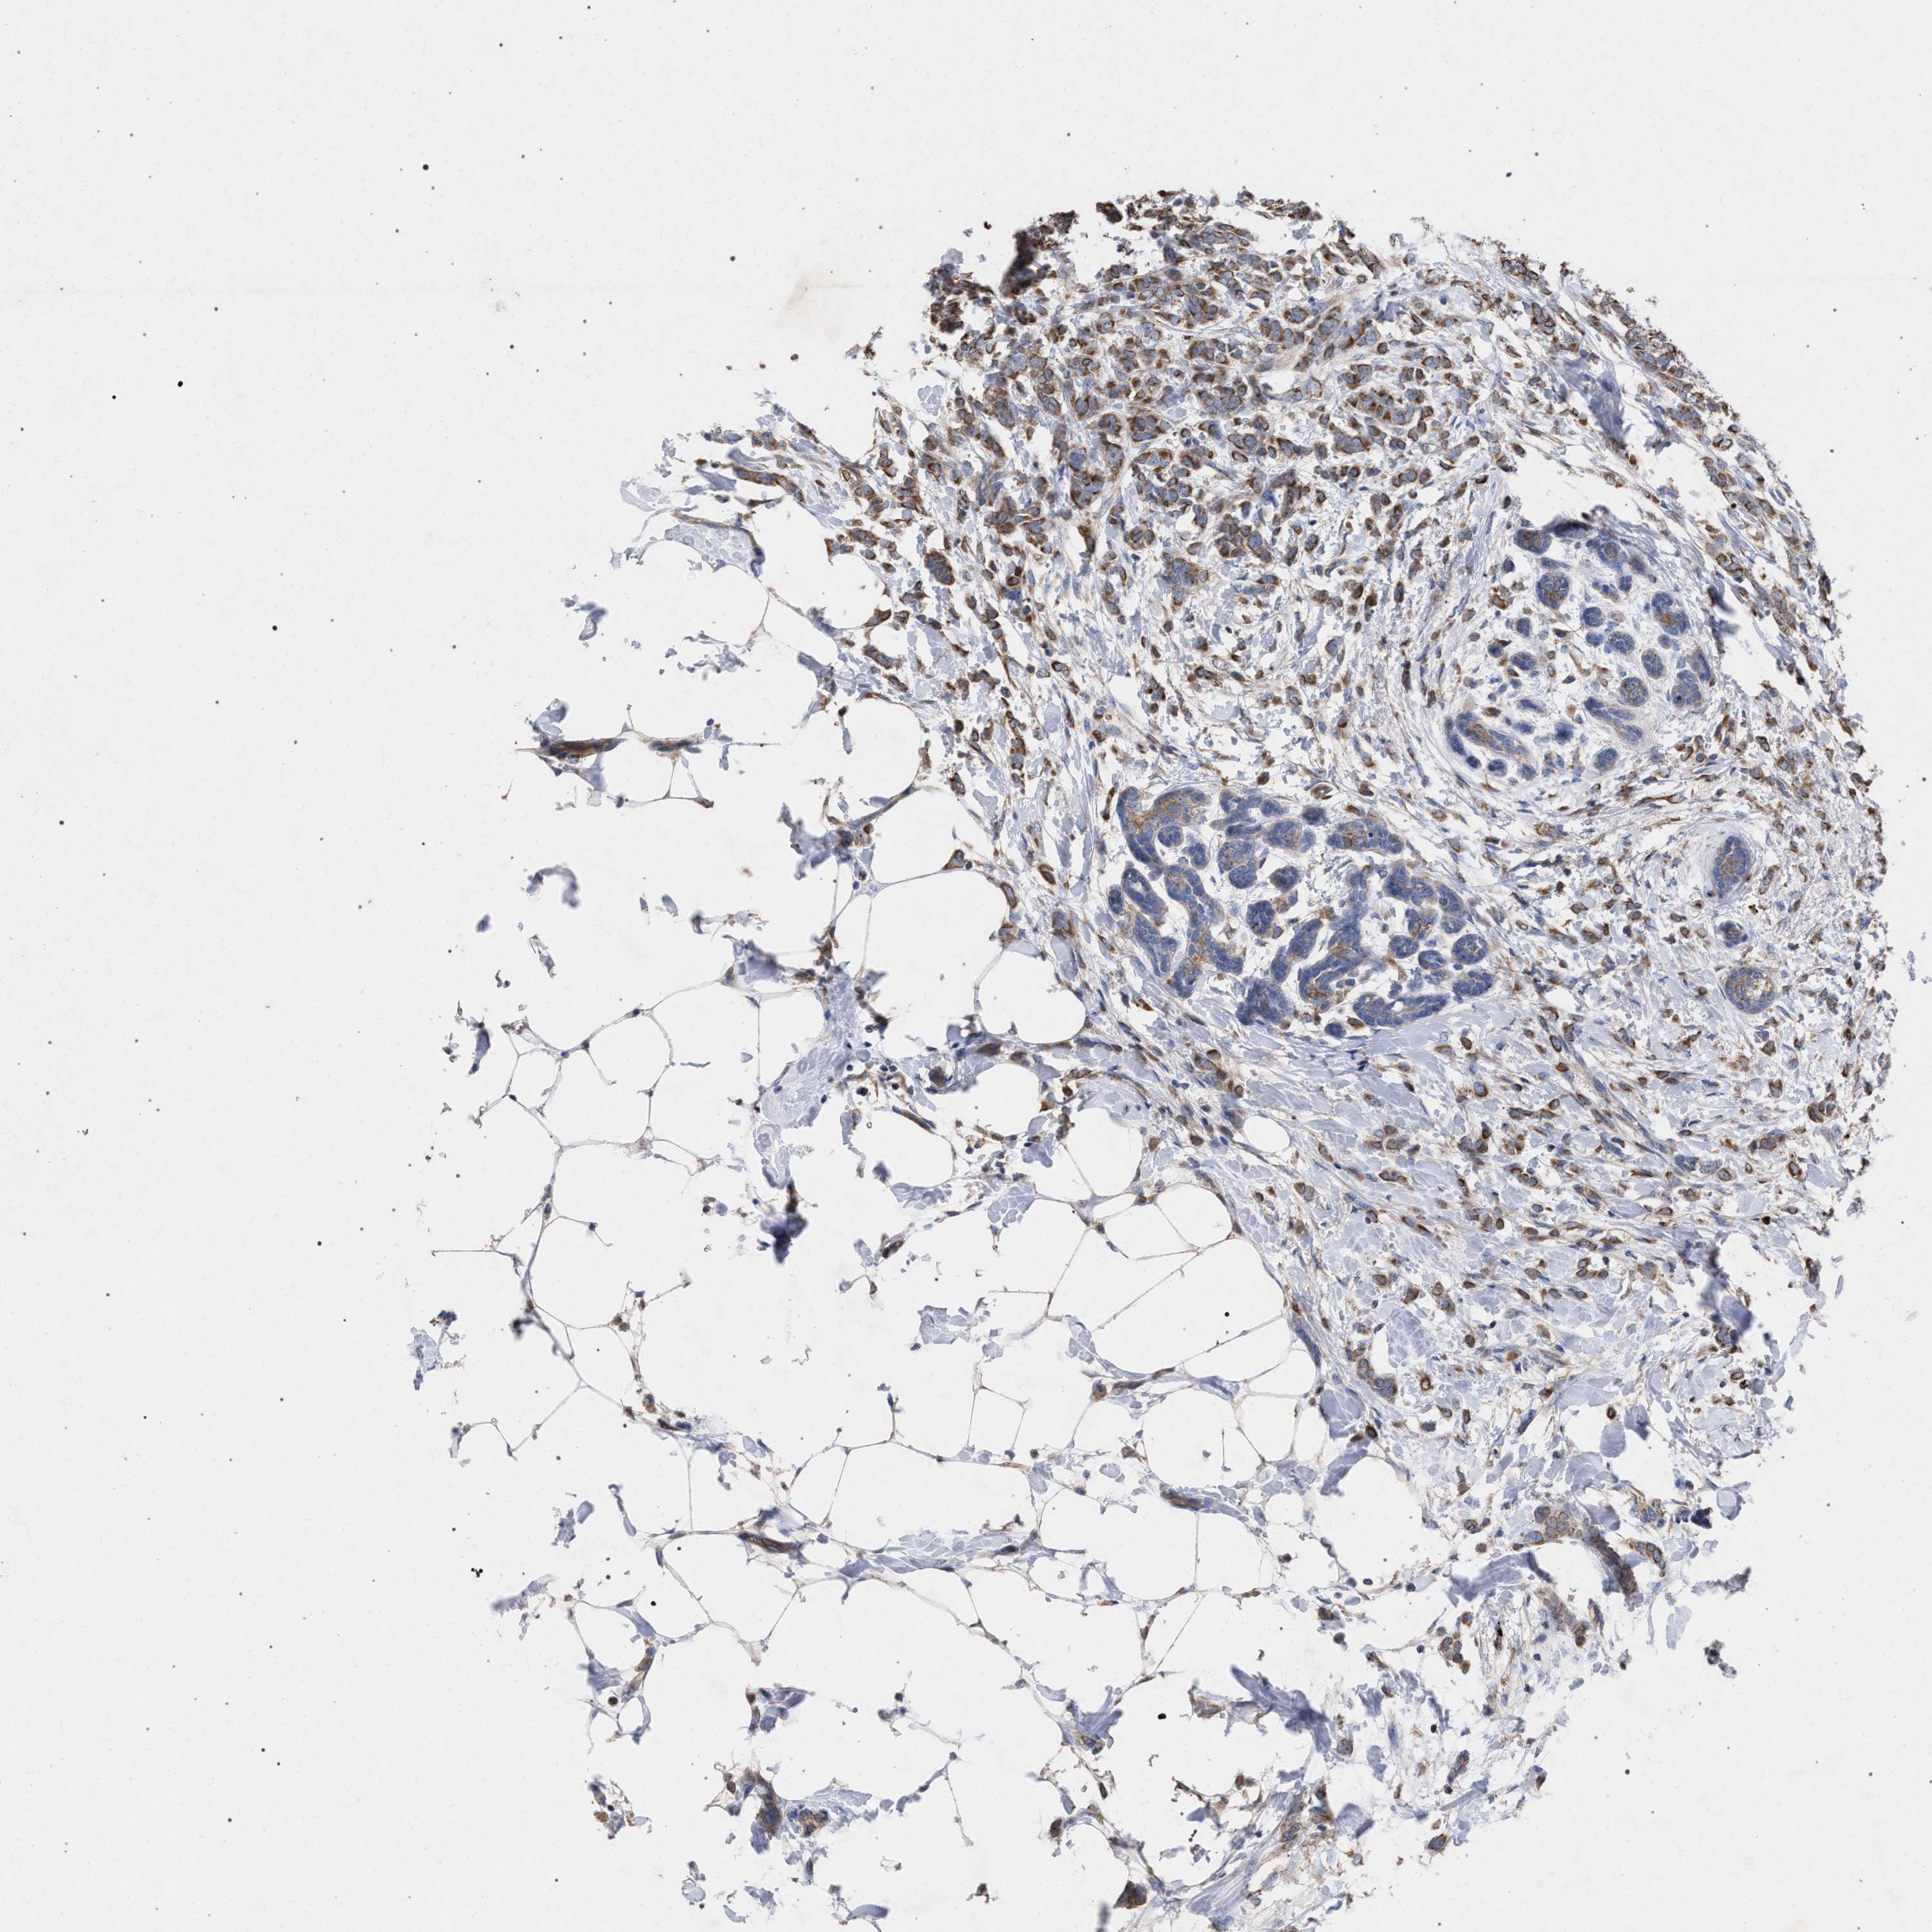

CANCER BREAST CANCER Show tissue menu

BRCA TCGA BRCA VALIDATION PROTEIN EXPRESSION